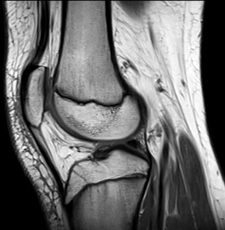

• MRI of a kneeChoose the correct imaging testMRI and ultrasound are safer alternatives to X-rays and CT scans, but are not always the most appropriate tools.